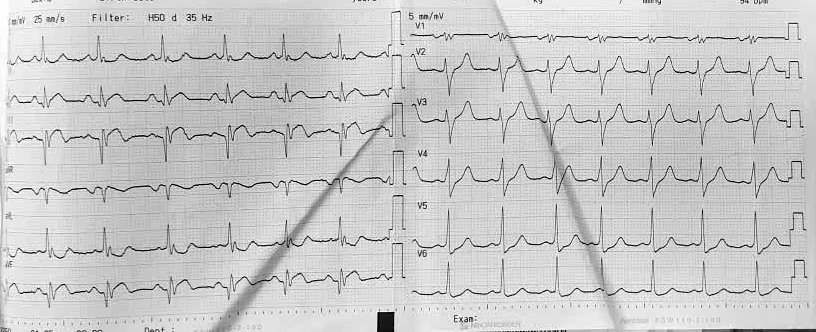

Điện tim bệnh nhân Q. trước mổ bình thường.

Vài giờ sau mổ, bệnh nhân bất ngờ xuất hiện đau ngực trái lan ra vai và cánh tay, kèm vã mồ hôi, khó thở. Nhận thấy bệnh nhân có diễn biến bất thường, các bác sĩ nhanh chóng hội chẩn chuyên khoa Tim mạch, kết quả điện tâm đồ cho thấy bệnh nhân nhồi máu cơ tim cấp thành dưới sau mổ nội soi cắt túi mật - Loét hành tá tràng đang liền sẹo.

Nhịp tim bất thường trên điện tâm đồ của bệnh nhân Q. sau phẫu thuật.